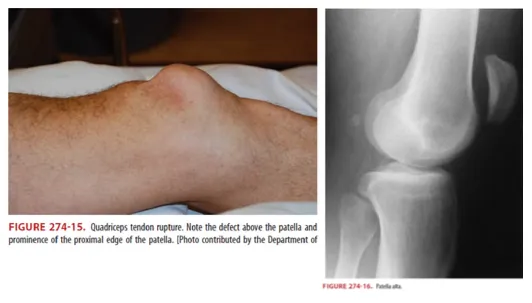

G6. Quadriceps or patellar tendon rupture

•

(2) Tendinitis 과거력, steroid 사용이 risk factor

(3) Patella proximal or distal에서 tendon rupture에 따라 defect가 만져짐

(4) Patella alta (Figure 274-14) : Lat. x-ray에서 high-riding patella 소견